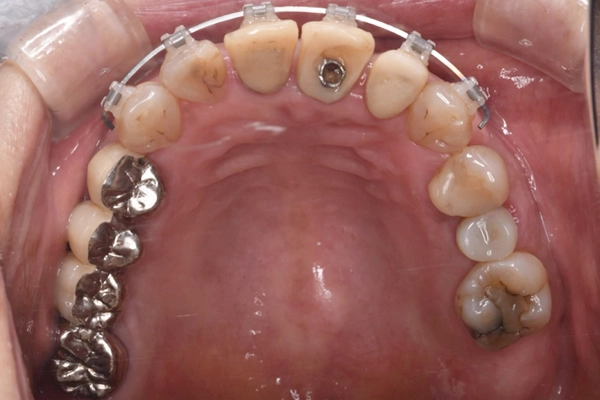

上顎と下顎の前歯の叢生(ガタガタした歯並び)の改善、左上2番の歯列改善のため右上3番〜左上3番、右下3番〜左下3番に唇側ブラケットを装着し歯列改善を行いました。

上顎はインプラントをアンカー(支点)として唇側傾斜、移動させ、下顎は右下1、2番と左下1、2番を中間地点くらいに移動させました。

矯正治療の様子

治療前の上顎の様子

です。

矯正を行ったことで、上顎のアーチも整ってきていることがわかります。